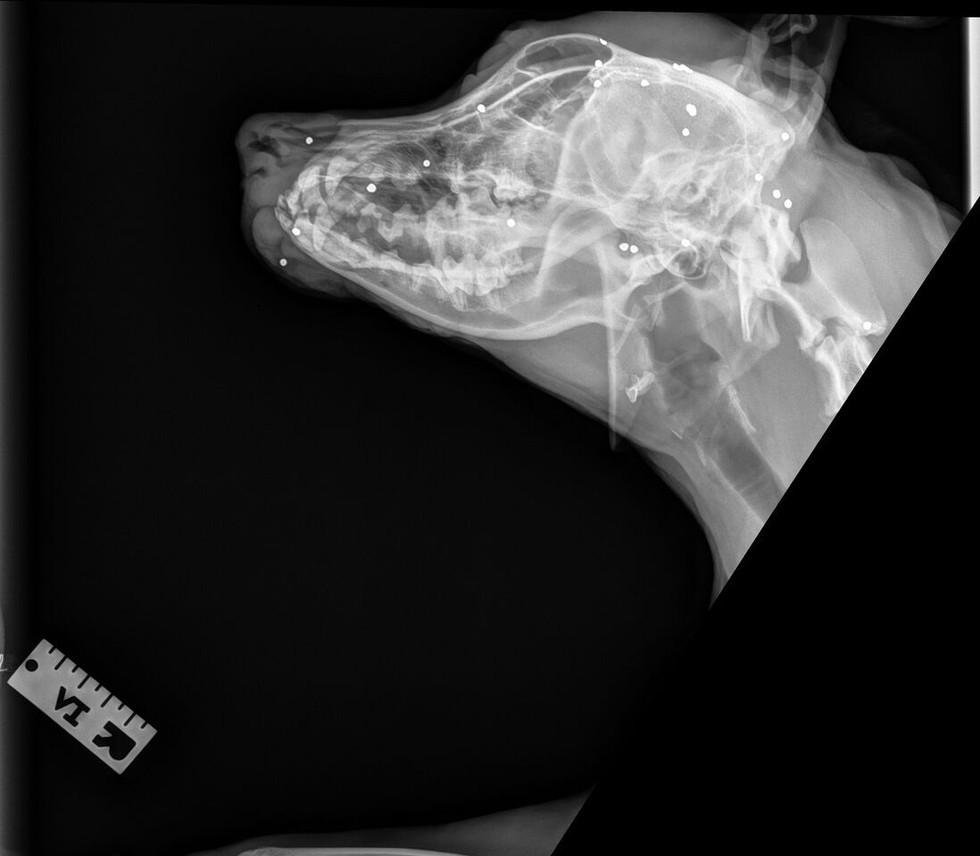

En effet, la chienne a de gros problèmes quand il s'agit d’interagir et de sociabiliser avec les humains. Elle est réticente à sortir et est angoissée au contact de ces derniers. Personne ne parvenait à comprendre pourquoi.Jusqu'au jour où, lors d'une consultation de routine, un groupe de vétérinaires a enfin résolu le mystère. Suite à une radio, ils découvrirent ce qui se cachait à l'intérieur de Mama...

Les vétérinaires constatent alors de nombreuses petites bosses répandues sur l'ensemble de son coprs. Cindy Szczudlo, la directrice de l'équipe médicale, raconte au siteThe Dodo:

Nous lui avons fait passer une radio et nous avons découvert que Mama était criblé de petites balles de fusil de chasse, ce qui explique probablement pourquoi elle était si craintive à l'extérieur. Quelqu'un a dû lui tirer dessus par le passé.

Ces petites munitions généralement utilisées pour chasser les oiseaux ; leur présence en grand nombre dans le système de Mama reste donc inexpliquée.